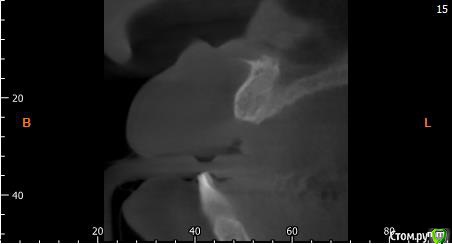

Собственно ситуация такая. Фронтальные зубы сверху были потеряны в результате серьезной травмы,  ! Фактически полное отсутствие костной ткани в области фронтальных зубов и по толщине и по высоте. Пациент ходит с чс протезом и хочет нечто несъемное.

Интересует как лучше это сделать при таких объемных дефектах.  Мои мысли первым этапом сосидж, потом 4 импланта. Но как быть с временным протезированием?